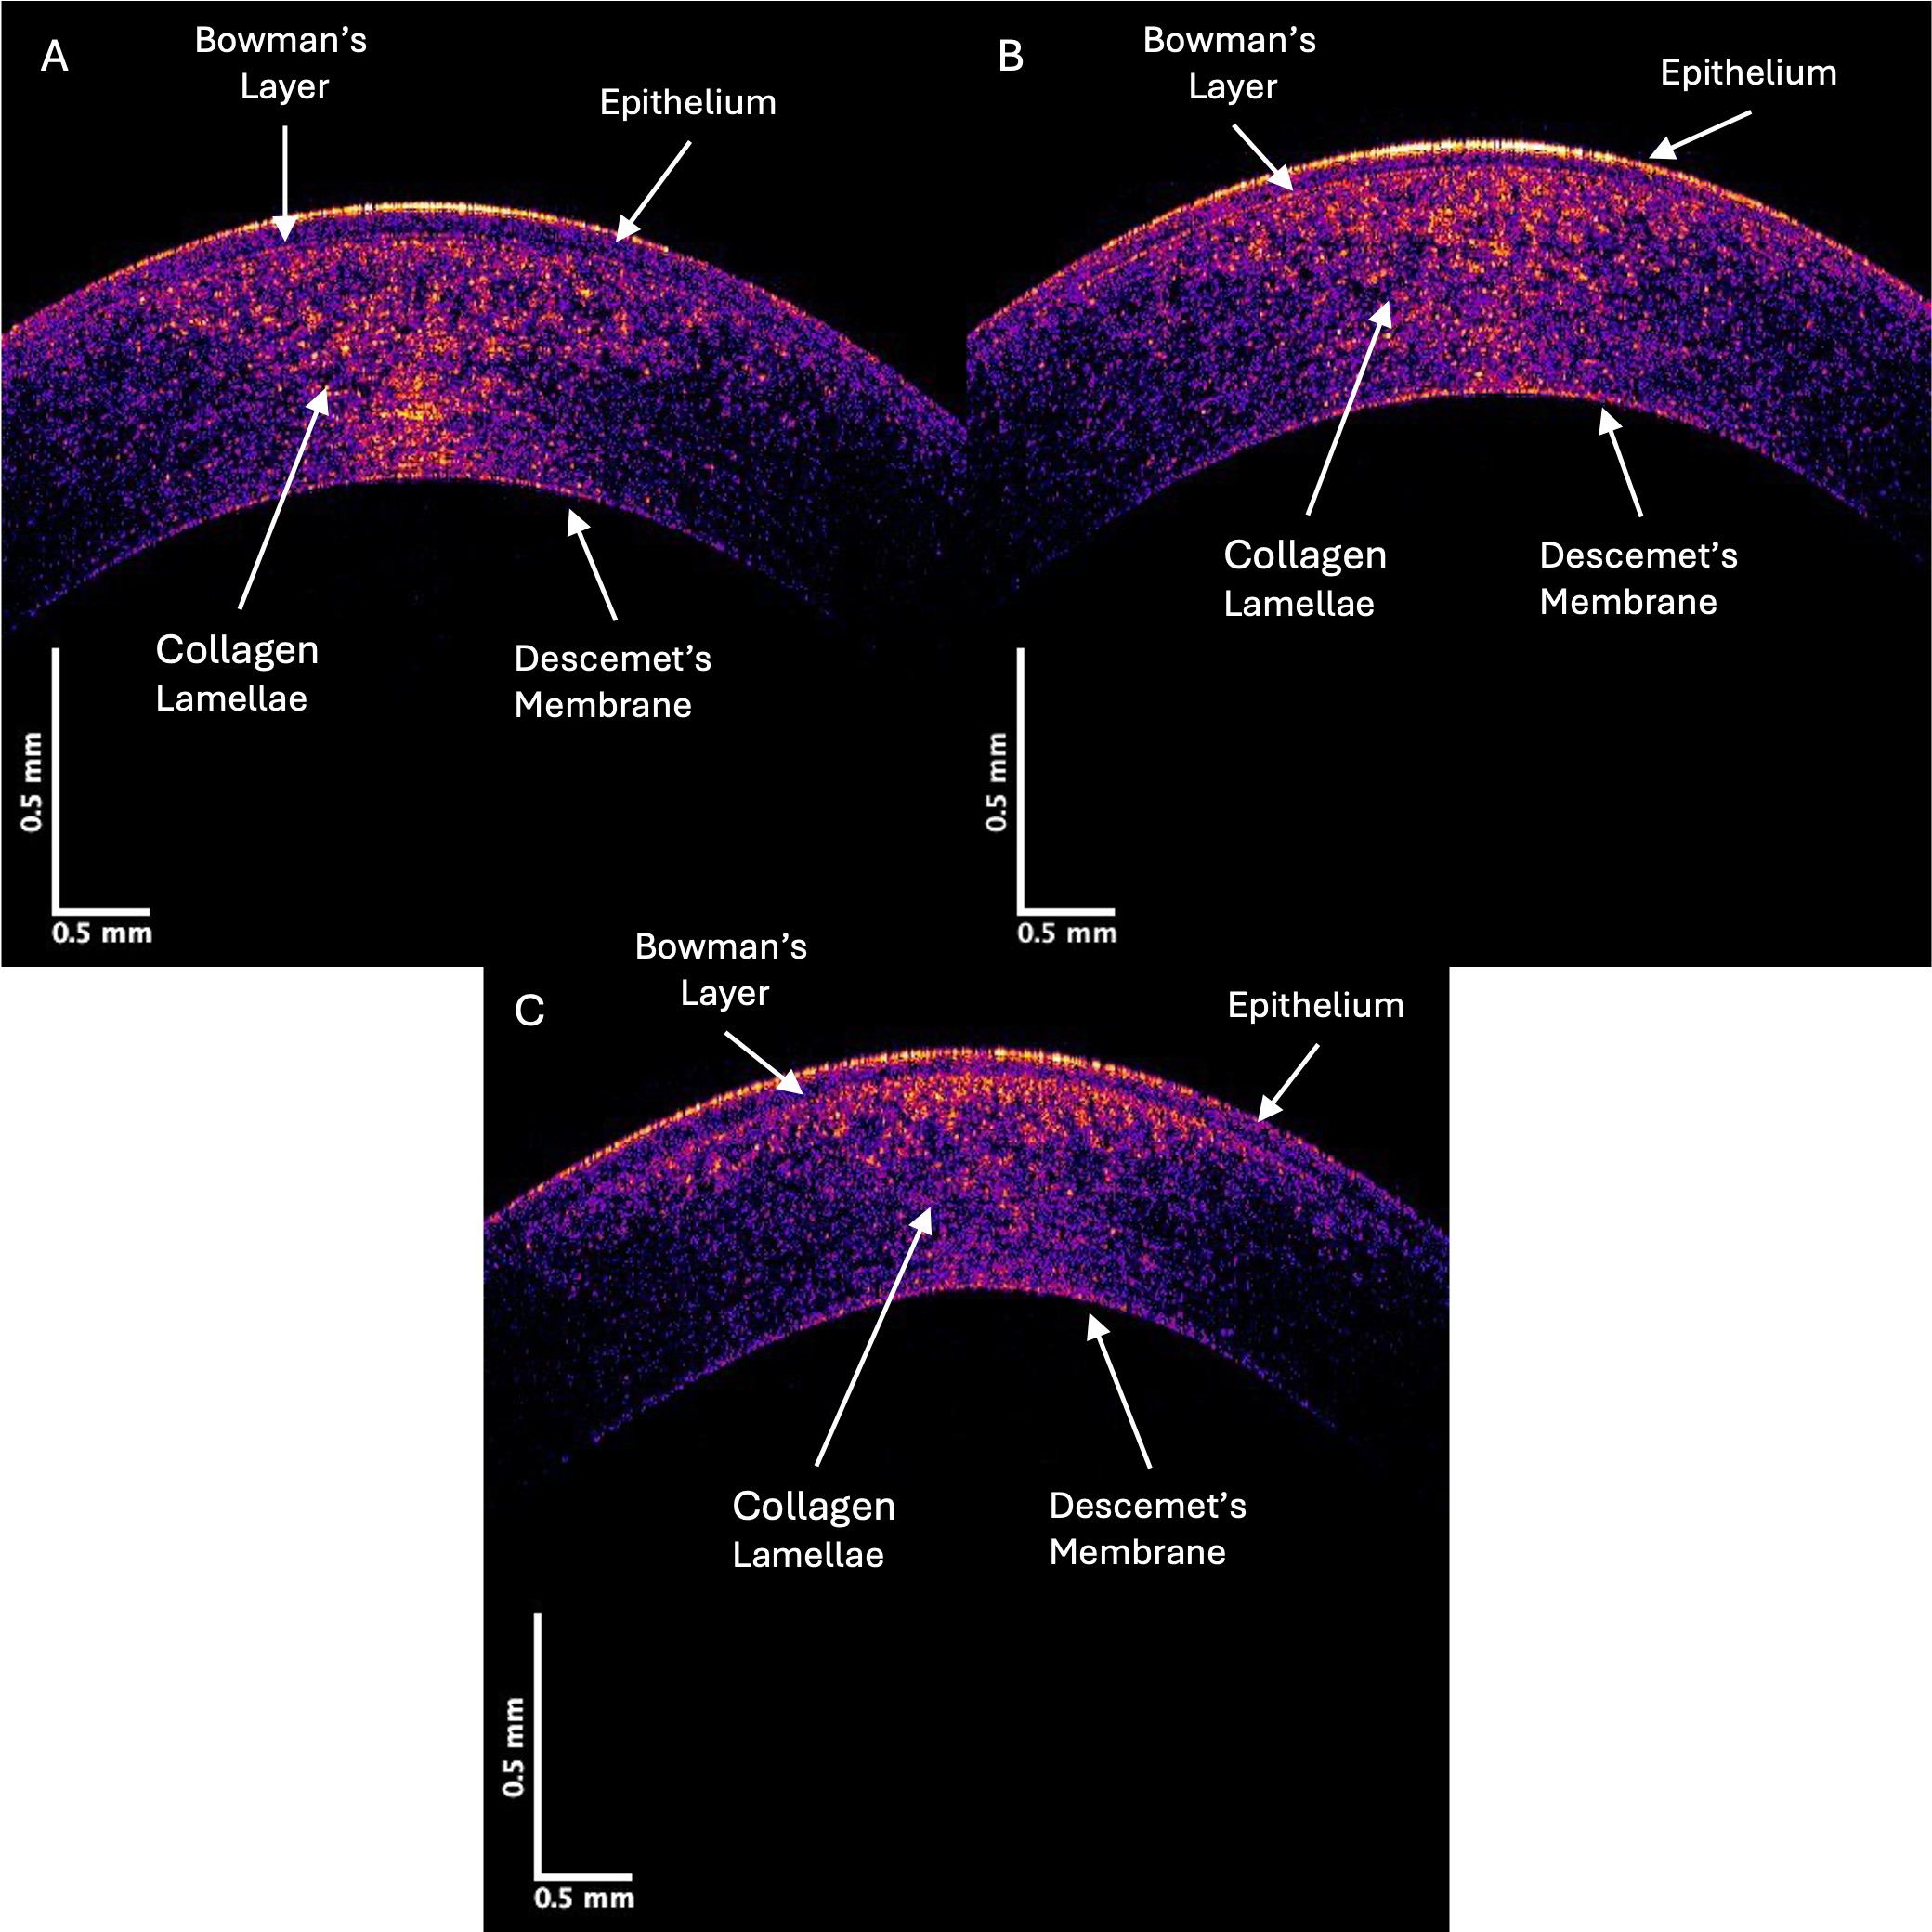

Fig. 1 shows typical OCT color-coded images of control (A), Stage II (B), and Stage IV (C) KC corneas. The locations of the epithelium, Bowman’s layer, corneal lamellae, and Descemet’s membrane are marked on the images. Notably, the yellow and pink areas in the posterior regions of the Stage II and IV KC corneas were decreased compared to the control. Based on prior skin and skin lesion studies [9, 10, 12], the yellow and pink areas represent reflected light from cells, and the blue regions illustrate reflected light from the collagen fibrils.

Fig. 1. Color-coded OCT image of typical control (A), Stage II (B), and Stage IV (C) KC central corneas. Note the qualitative decrease in the yellow, pink, and blue intensities in regions in the Stage IV image compared to the control, which indicates a loss of cells (yellow and pink) and collagen fibrils (blue).